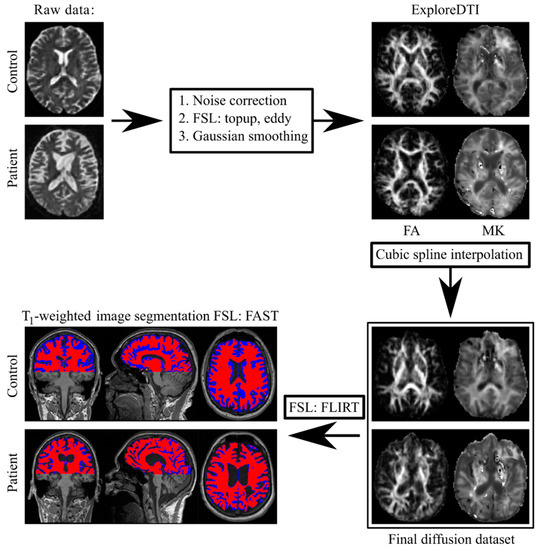

2.3. Image Analysis